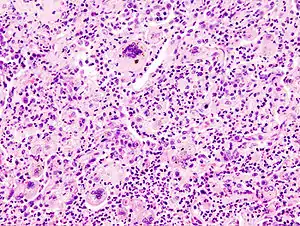

| Microscopic image of aspiration pneumonia in an elderly person with a neurologic illness. Note foreign-body giant cell reaction. | |